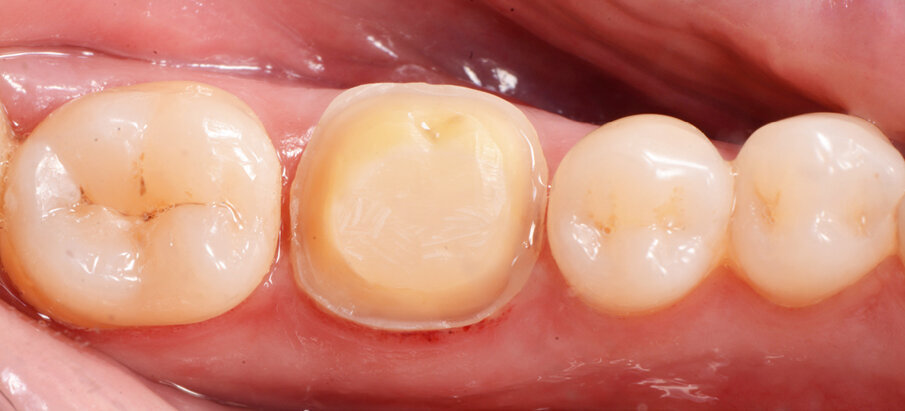

Fig. 2: Situation after composite build-up (Tetric N-Ceram Bulk Fill) and preparation

A 45-year-old male patient presented to the practice with a restoration on tooth 46. The tooth had been endodontically treated and was temporized with a filling (Fig. 1). The temporary was removed, the tooth built up with Tetric N-Ceram Bulk Fill and then prepared for the crown restoration (Fig. 2). An impression was taken with a one-step two-phase impression technique using putty and light-body silicone. After scanning the model, the crown was designed in the software suite (inLab, Dentsply Sirona) and milled from an IPS e.max® lithium disilicate block (Fig. 3). After the crystallization firing the crown was stained and glazed (Fig. 4).